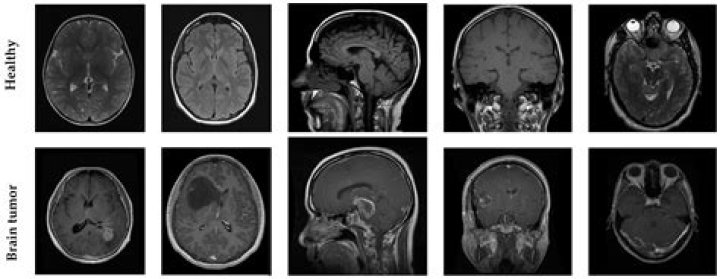

In general, diagnosing a brain tumor usually begins with magnetic resonance imaging (MRI). Once MRI shows that there is a tumor in the brain, the most common way to determine the type of brain tumor is to look at the results from a sample of tissue after a biopsy or surgery.

Diagnosing a brain tumor usually involves a neurological exam, brain scans and a biopsy, if it can be done safely. A neurological exam may include a variety of tests to evaluate neurological functions such as balance, hearing, vision and reflexes.